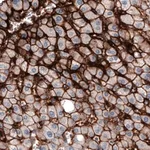

Prestige Antibodies® 라인의 CL3771 클론 단일클론 항체로, 인간 SLCO1B3 단백질을 인식합니다. 정제된 IgG1 형태의 1차 항체이며, 면역조직화학에 적합합니다. −20°C에서 보관하며, 습한 얼음 상태로 배송됩니다.

Prestige Antibodies® Powered by Atlas Antibodies, clone CL3771.

| Technique(s) | Immunohistochemistry (1:500–1:10000) |

Merck Monoclonal Anti-SLCO1B3 antibody produced in mouse

671,800원